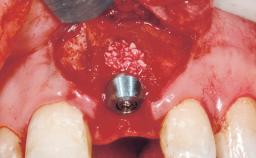

Immediate Flapless Placement of an Implant in a Maxillary Left Central Incisor Site

A 29-year-old female patient presented for treatment to replace the upper left central incisor tooth with an implant- supported restoration. The tooth had been intermittently symptomatic for the previous 12 months. The tooth had originally suffered trauma about 15 years previously. Several endodontic treatments had been performed, including an apicectomy procedure to retain the tooth. The patient was healthy and a non-smoker. She had reasonable expectations in regard to esthetic outcomes and the risk of marginal tissue recession following treatment. At medium smile, the gingival margins of the upper teeth were visible, with a display of 3 to 4 mm of the gingival margins. Gingival recession of tooth 21 and a discrepancy in the gingival levels between teeth 11 and 21 was observable during normal speech and smile.

Placement Protocol Immediate implant placement

Tooth Site Maxillary incisor or canine

Socket Morphology Single-root socket

Socket Integrity Damage to one or more bone walls